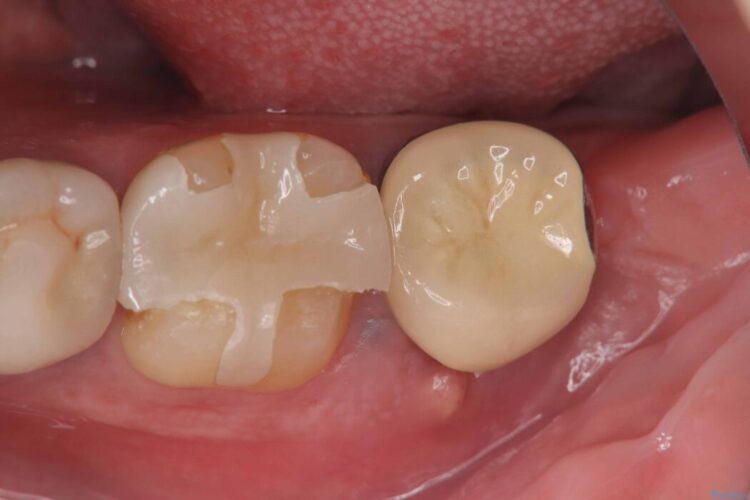

銀歯の段差の改善、ラバーダム防湿下で行うセラミックインレー治療

銀歯の段差の改善、ラバーダム防湿下で行うセラミックインレー治療 ビフォー 銀歯の段差の改善、ラバーダム防湿下で行うセラミックインレー治療 アフター

当院でメンテナンスに通われている患者様の症例です。